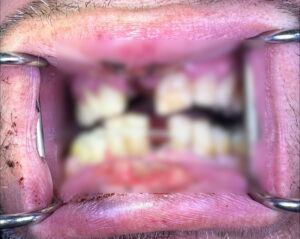

«Έχω χάσει δύο δόντια και έχουν σπάσει ακόμη τέσσερα, δεν μπορώ ούτε να μιλήσω ούτε να φάω», λέει στο newsit.gr.

Η μπαταρία πετάχτηκε στην άλλη άκρη του δωματίου στην πόρτα και αν δεν είχε φύγει ο γιος μου θα τον είχε χτυπήσει, σκεφτείτε πήρε φωτιά η μπαταρία και κάηκε κ η ντουλάπα. Έχω πάθει σοβαρή ζημιά. Αυτή την στιγμή έχω χάσει δύο δόντια και έχουν σπάσει ακόμη 4 και τα έχουμε στερεώσει με σιδεράκια, μήπως και ξανά κολλήσουν. Μετά έκανα ράμματα στο στόμα και στα ούλα γιατί έχανα πολύ αίμα. Δεν μπορώ να μιλάω αλλά ούτε να τρώω, πονάω. Αλλά σχετικά με το κατάστημα που πήρα το ηλεκτρονικό τσιγάρο, έχω βάλει την δικηγόρο μου να δούμε τι ενέργειες μπορούμε να κάνουμε».